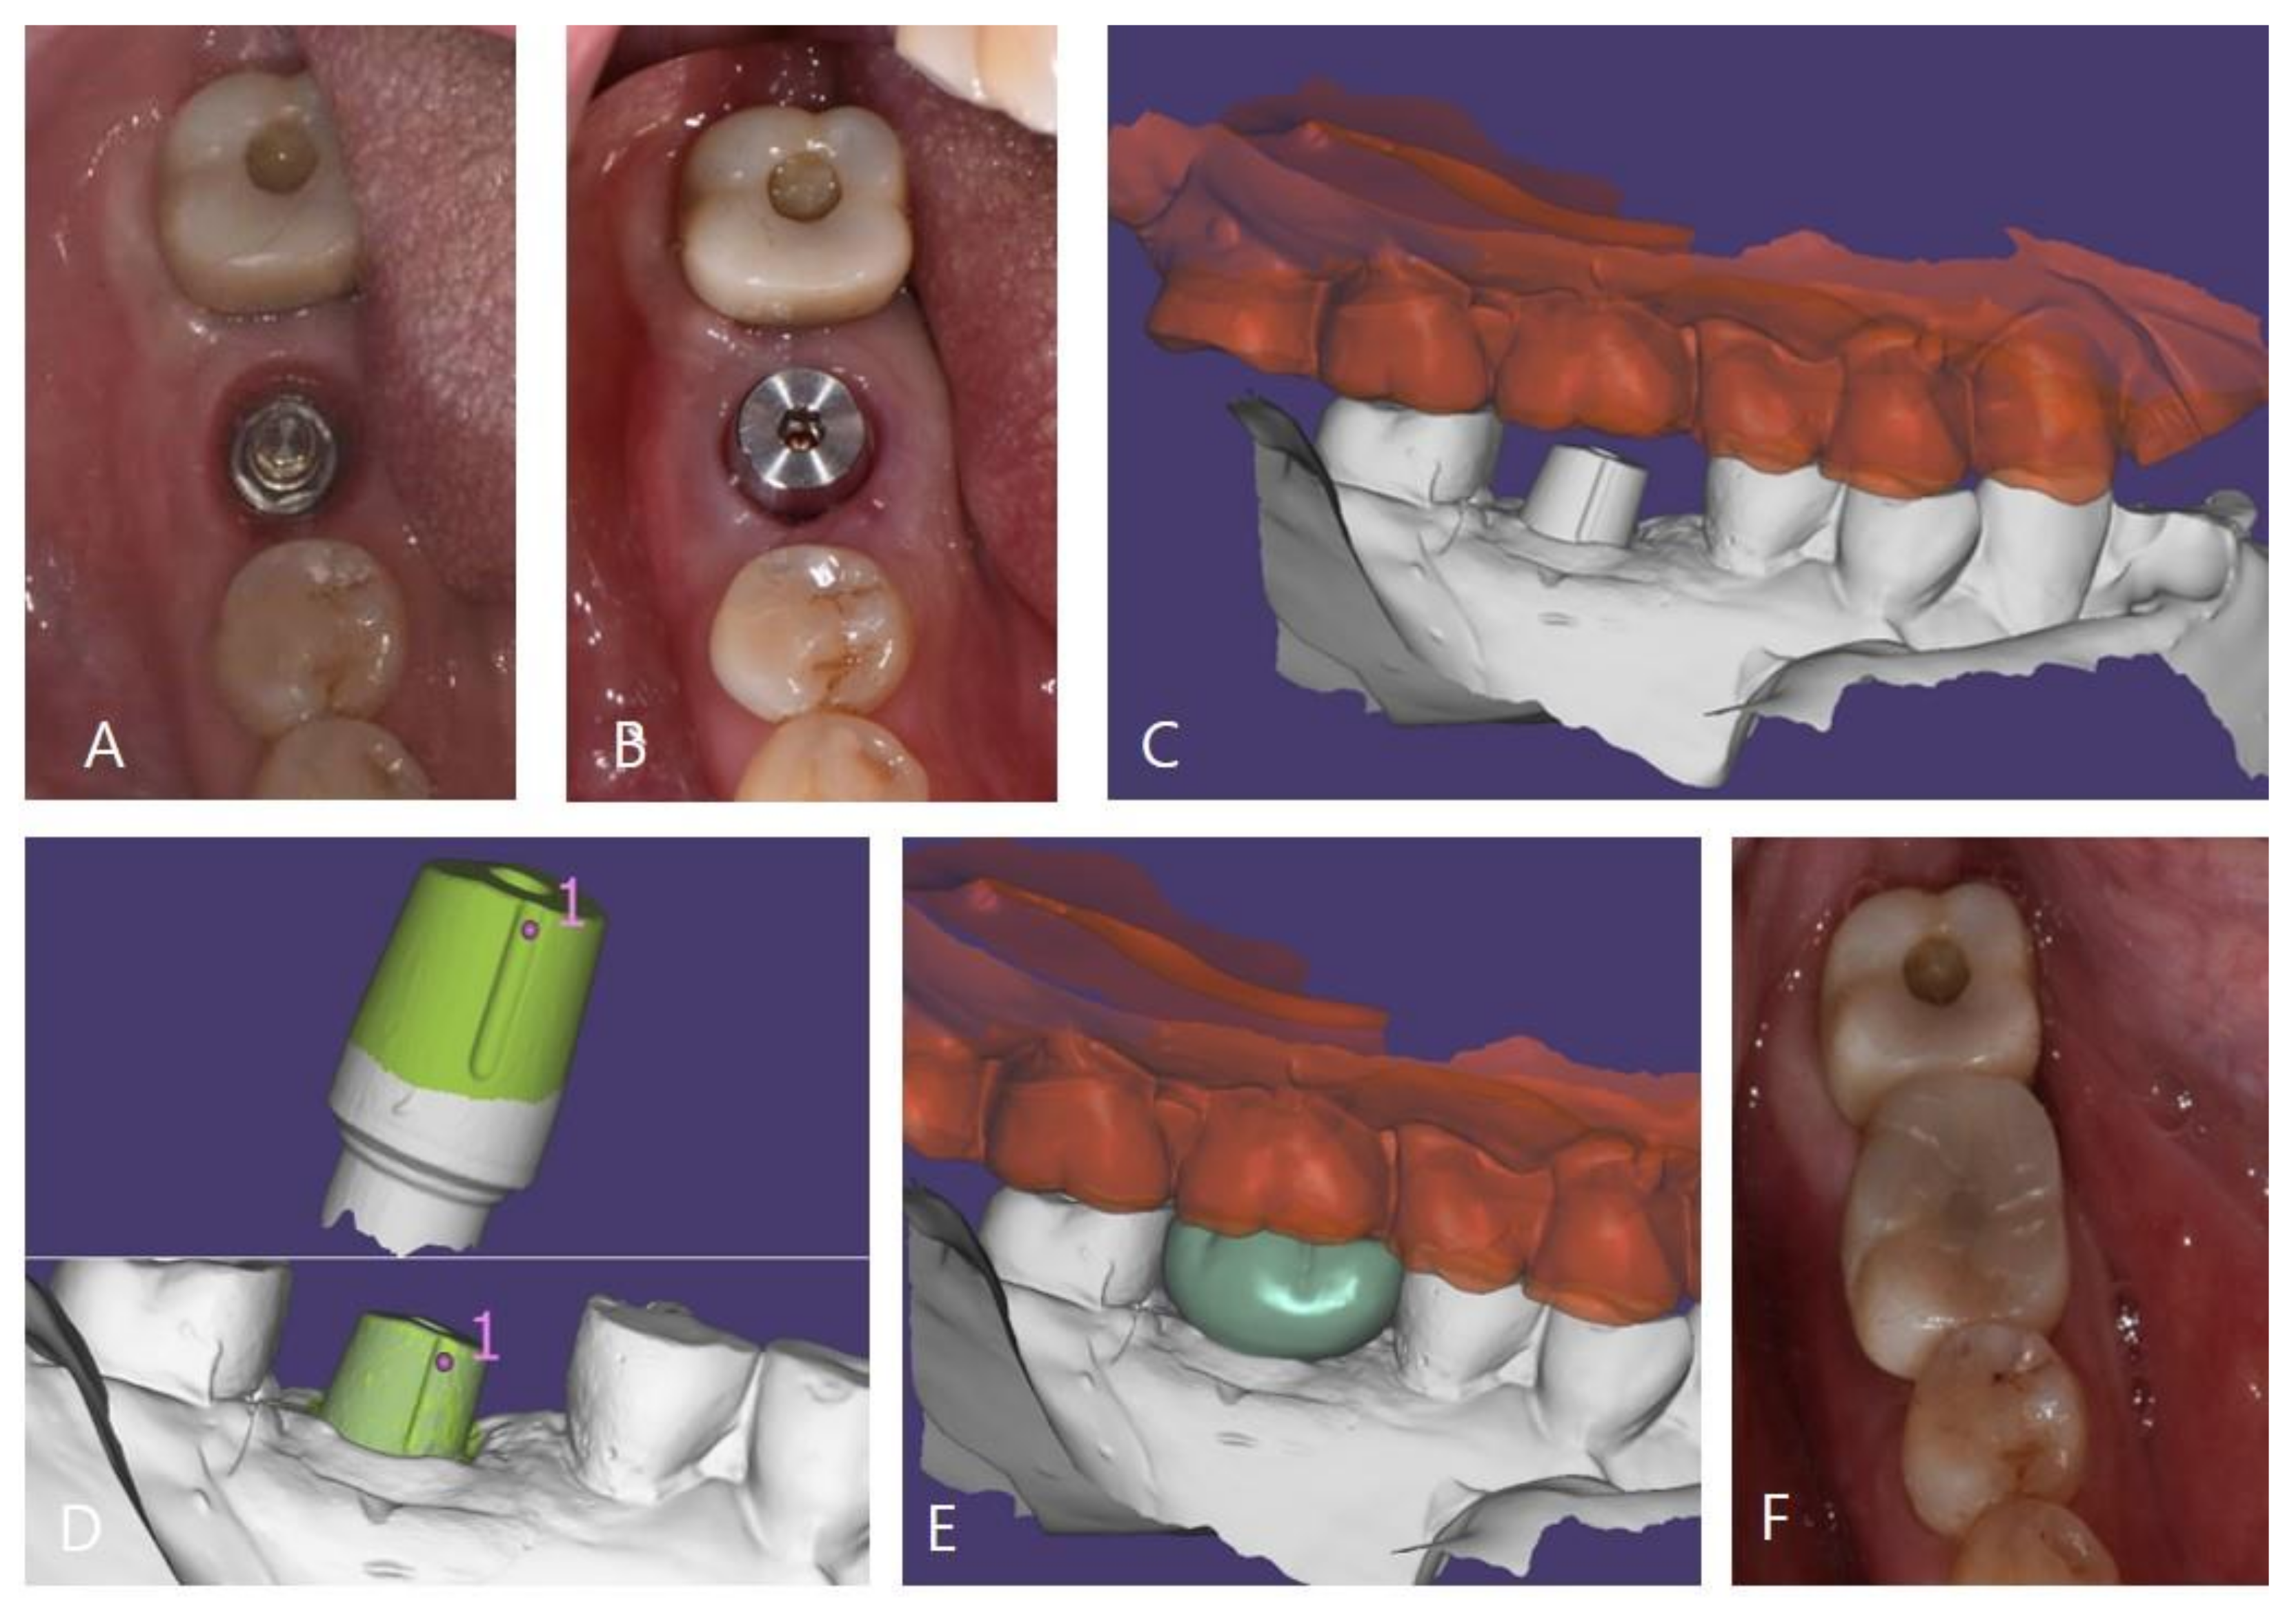

In the MLA group, the abutment was tightened to 35 N/cm according to the manufacturer’s instructions before taking an impression for the prosthesis and then the cap was attached to the abutment by using a dedicated tool. In the MLF group, the ML system was included in the fixture and, thus, the cap was directly attached to the implant. The subsequent impression-taking process was identical in both groups. The impressions were obtained by using silicone impression material (Imprint II VPS, 3M ESPE, Seefeld, Germany) and a fabricated master cast was scanned by using a 3D scanner (Trios 3, 3Shape, Copenhagen, Denmark). Zirconia crowns were manufactured by using a CAD-CAM system (Exocad DentalCAD, Exo-cad GmbH, Darmstadt, Germany) (Trione Z, Dio Implants, Pusan, Korea). After evaluating marginal suitability, esthetics, and occlusion in the oral cavity, the crowns were cemented to caps by using self-adhesive resin cement (G-CEM LinkAce; GC, Tokyo, Japan). Cemented crowns and caps were then removed by using a dedicated removal driver, excess cement was removed, and the crown margins were polished. Crowns cemented to caps were then reattached to abutments and access holes on occlusal surfaces were filled with a packable composite resin (Filtek Z350XT, 3M ESPE, St. Paul, MN, USA) (Figure 3) [26,33].

Figure 3. Prosthesis setting process of the ML system. (A): Exposed connection of the ML system, (B): attached cap, (C): model scanned data, (D): superimposing pre-scanned cap data onto model scanned data, (E): designed zirconia crown, and (F): zirconia crown on the cap fixed with resin cement.